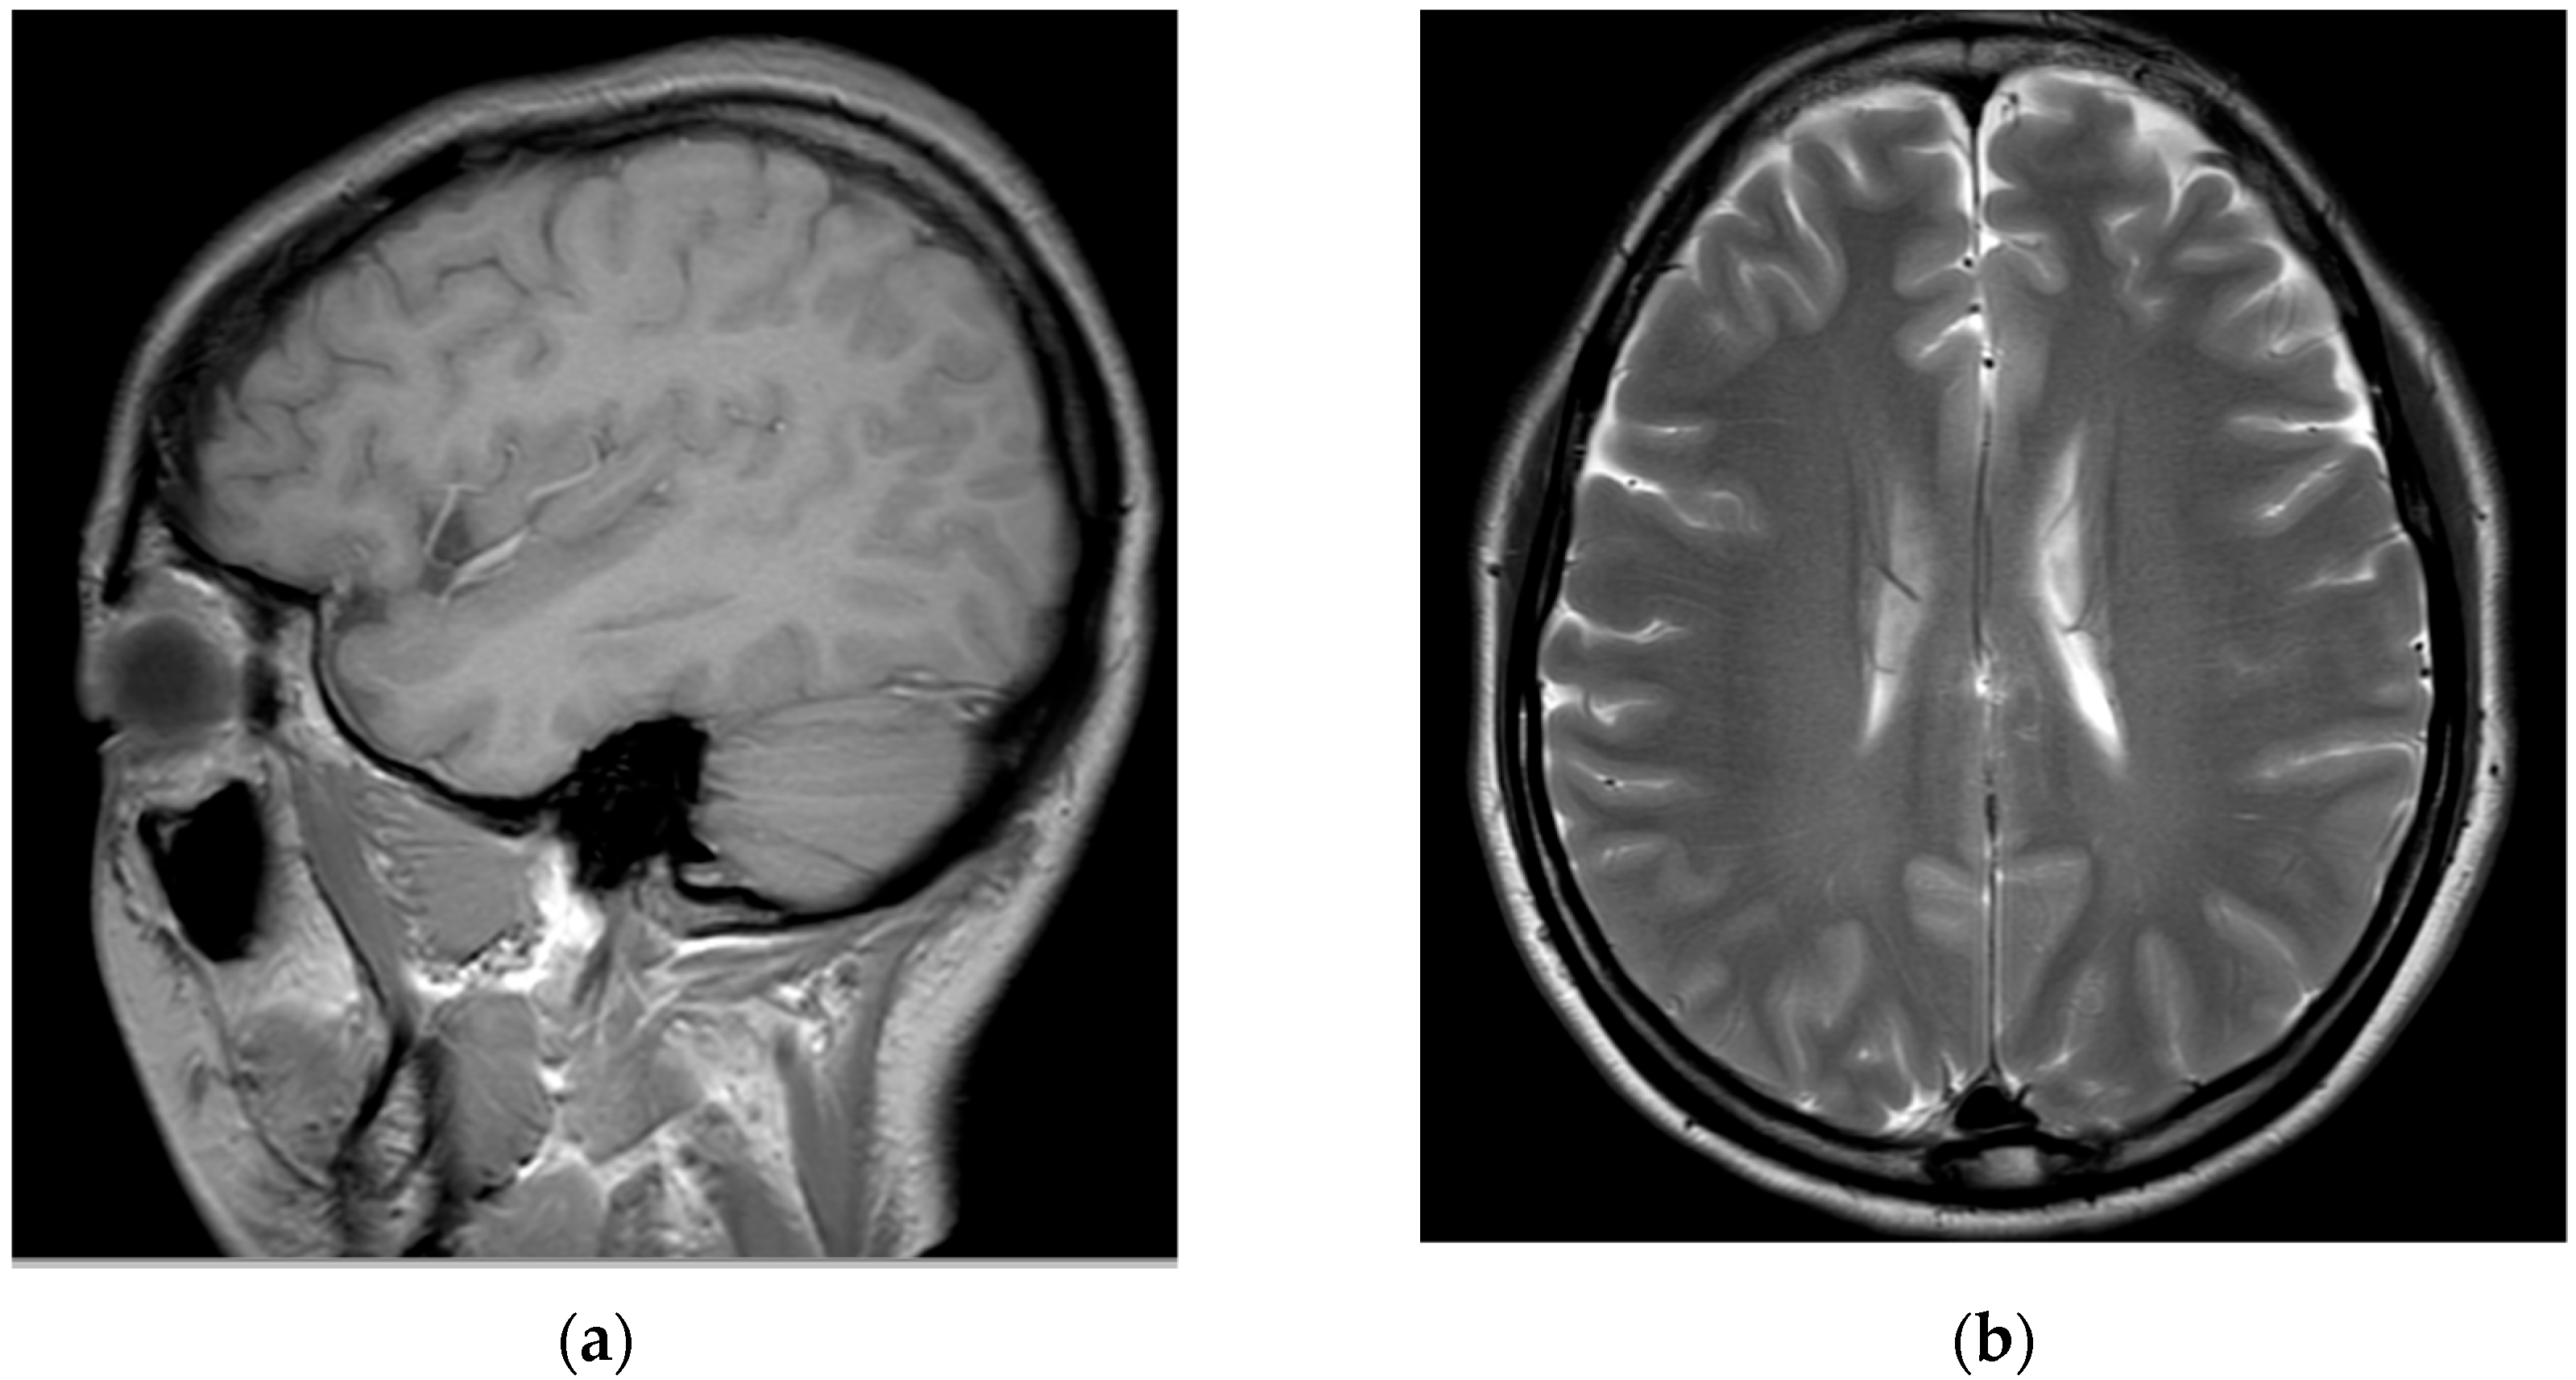

Medications, excluding steroids, were continued for 1 month after the procedure. The patient reported that their left upper arm motor weakness improved slightly (4/5); however, sensory changes persisted. Two months after the procedure, shoulder strength was almost fully restored (5/5), left-hand motor weakness slightly improved further (4/5), and sensory function had almost returned to normal; however, the patient complained of persistent paresthesia in her left hand. At 3 months after the procedure, her left-hand motor weakness showed almost complete recovery (5/5); however, abduction of her fifth finger diminished to 4/5, and the decreased sensation in the dorsum of the left hand persisted. Six months after the procedure, abduction of the fifth finger continued to decrease and sensory deterioration in the dorsum of the left hand remained. As detected during the follow-up MRI performed 6 months post-procedure, the T2 high signal intensity in the left central intramedullary region decreased compared to that observed previously; however, spinal cord swelling was still present, albeit reduced (Figure 4).

Figure 4.

Cervical spine magnetic resonance images obtained 6 months after the procedure: (a) T2-weighted sagittal image and (b) T2-weighted axial image of the C5/6 level. The extent of the left central intramedullary T2 high signal intensity (elongated lesion in the spinal cord) from the C4/5 to C7 levels slightly reduced. The spinal cord swelling is also reduced.

In addition, left C7/8 radiculopathy with acute denervation was confirmed by electromyography that was performed at 6 months after the procedure.